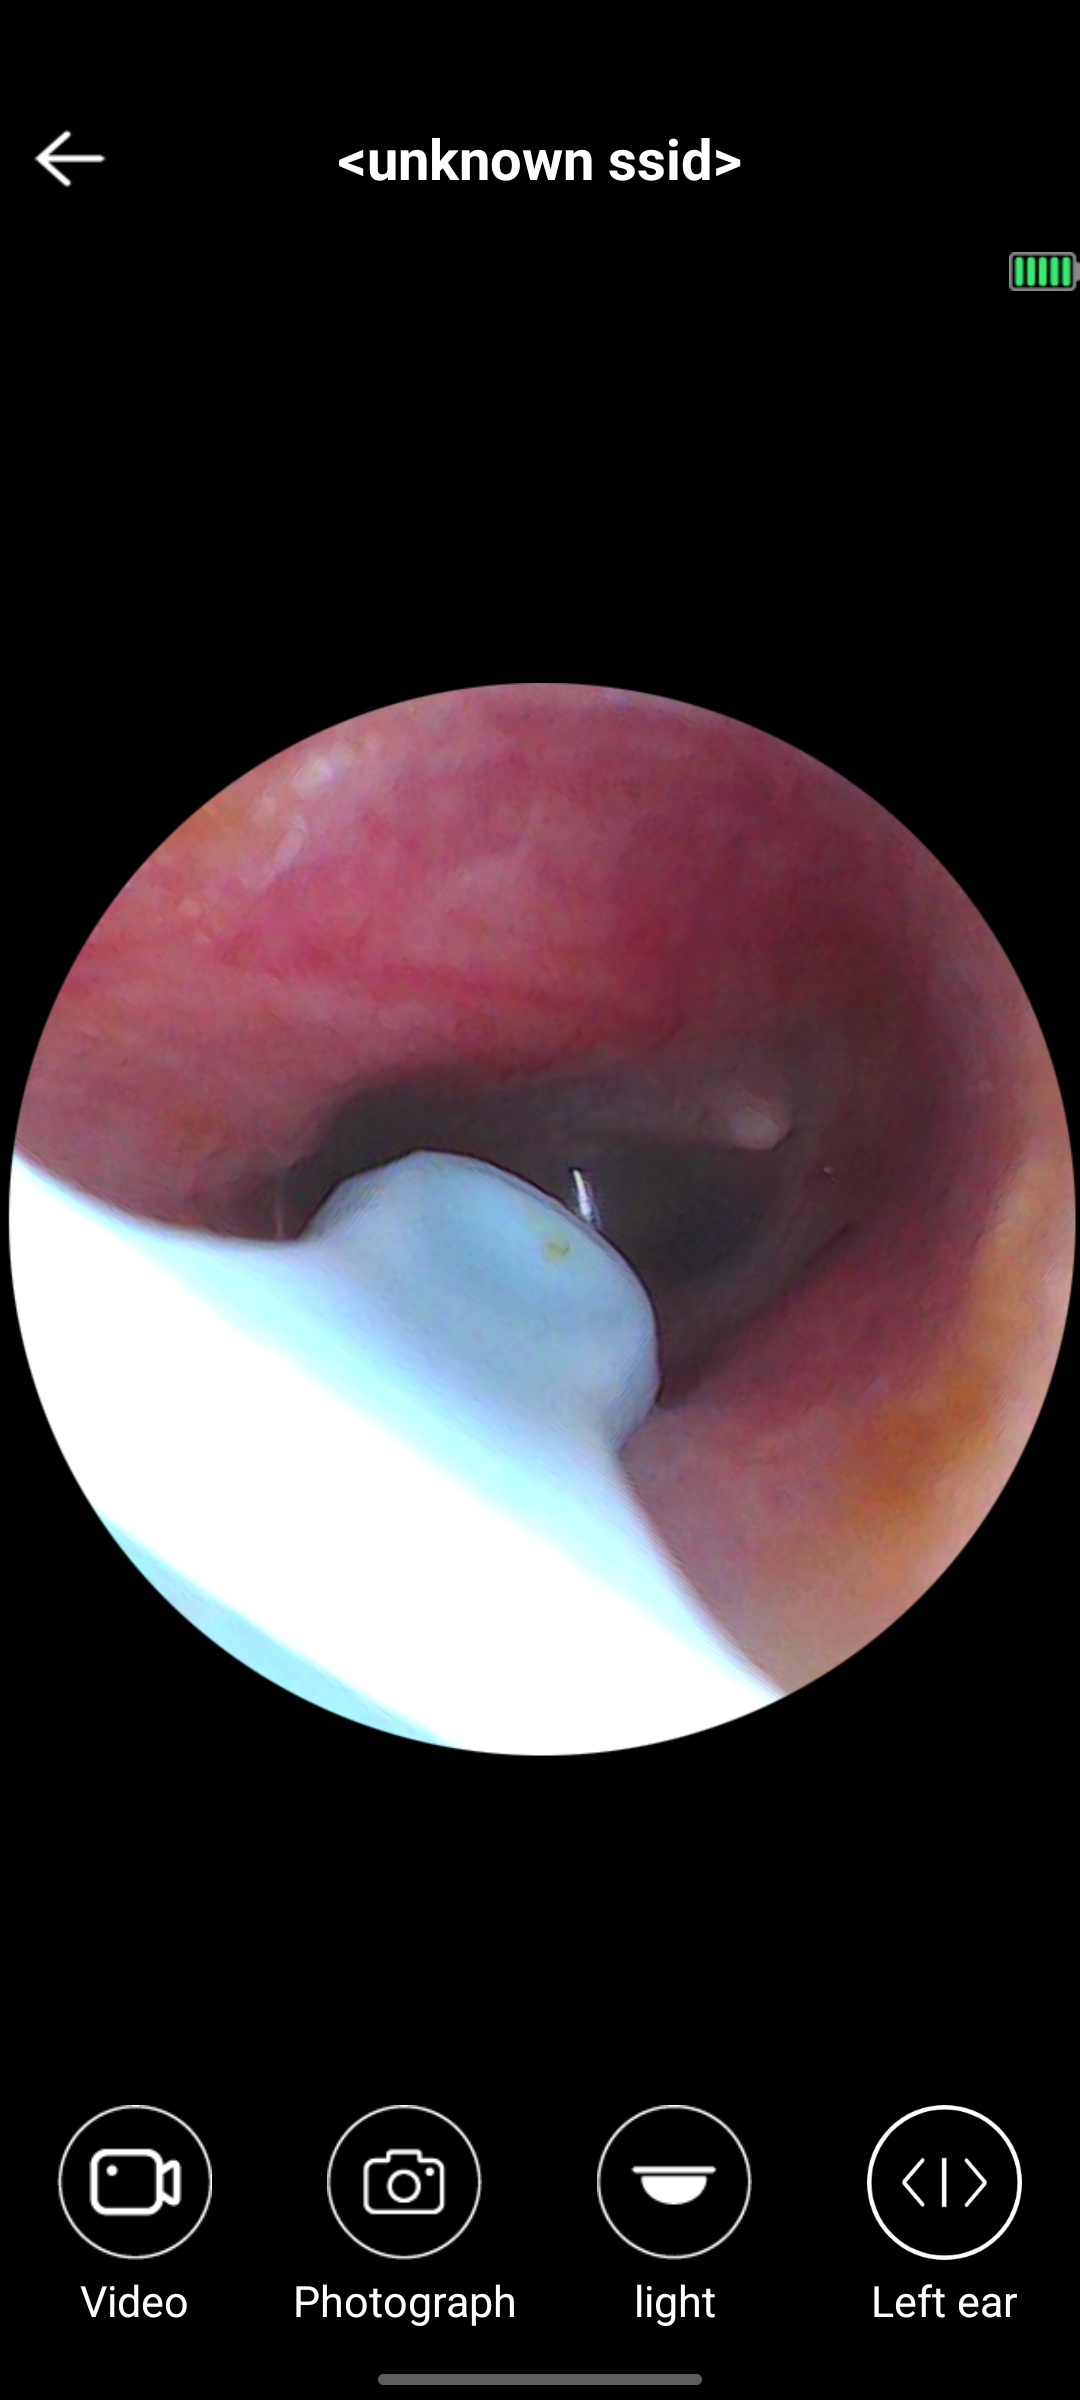

สวัสดีครับ มีจุดสีขาวในหูแบบนี้ปกติไหมครับ

มีก้อนสีขาวที่ข้างในรูหู

น้องชายมีก้อนสีขาวที่ข้างในหูค่ะ คล้ายก้อนสำลีที่อยู่ไม้แคะหู ถามก็บอกว่าไม่ได้แคะหูไม่ได้ทำอะไรติดไว้ในหู แม่พึ่งมาเห็นเมื้อกี้ ก้อนใหญ่เต็มหู แต่น้องชายบอกว่าไม่รู้สึกเหมือนมีอะไรอยู่ในหูเลย จิ้มก็ไ

สีขาวๆ ในหูที่เป็นก้อน อันตรายไหมคะ

ตอนนี้ยังได้ยินปกติ แต่ไม่กล้ายุ่งกับมันกลัวเจ็บคะ อยากทราบว่าอันตรายไหมแอบน่ากลัวนิดนึง